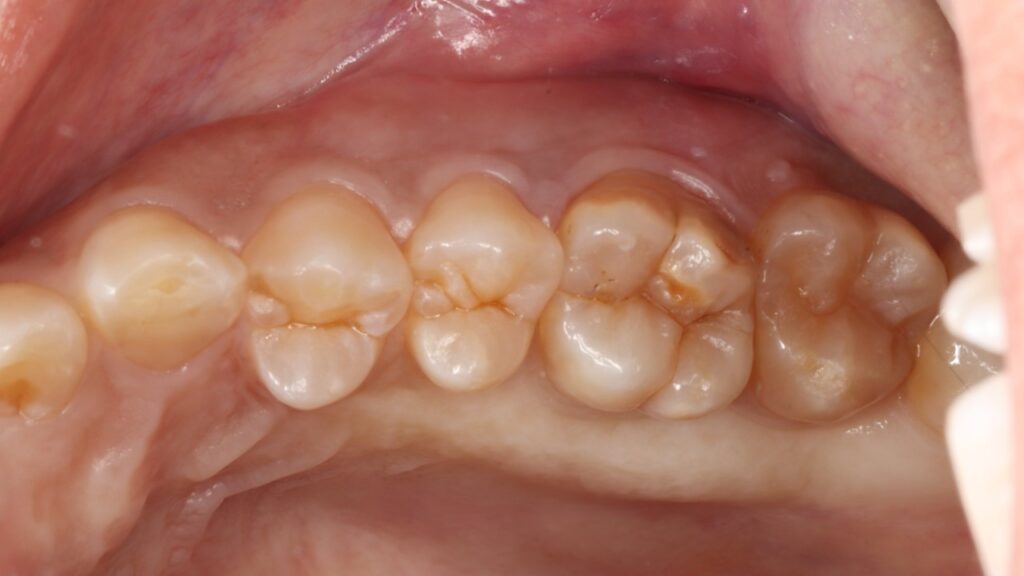

左上の奥歯に強い痛みを訴えて他院を受診したが何も問題ないと言われ、セカンドオピニオンを希望し当院に来院された患者様です。

虫歯も歯周病もなく、一見何の問題もないように見えましたがマイクロスコープ(顕微鏡)で詳しく確認すると噛む力に歯が負けて真っ二つに割れてしまっていました。

このように健康な歯が真っ二つに割れることはめったにないのですが、こうなると神経に触る様な強い痛みが出ますし、CTスキャンをとると上顎洞炎にもなっていました。